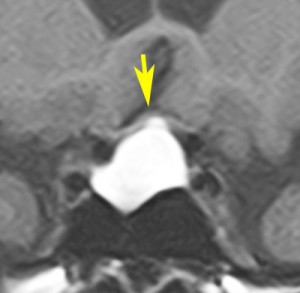

ラトケ嚢胞のMRIです。両耳側半盲という視野の障害(目がみづらい)で発症した女性のものです。左はT2強調画像と言います。右はガドリニウム造影剤を使ったものです。嚢胞のうすい壁だけが見えますが,中身は液体です。鼻孔から入って嚢胞をぷつんとつぶすだけの手術をします。薄い黄色の水のような液体が出ました。

手術後のMRIです。嚢胞はぺしゃんこになって視力は良くなりました。正常の下垂体は残っていてホルモンの障害もありません。